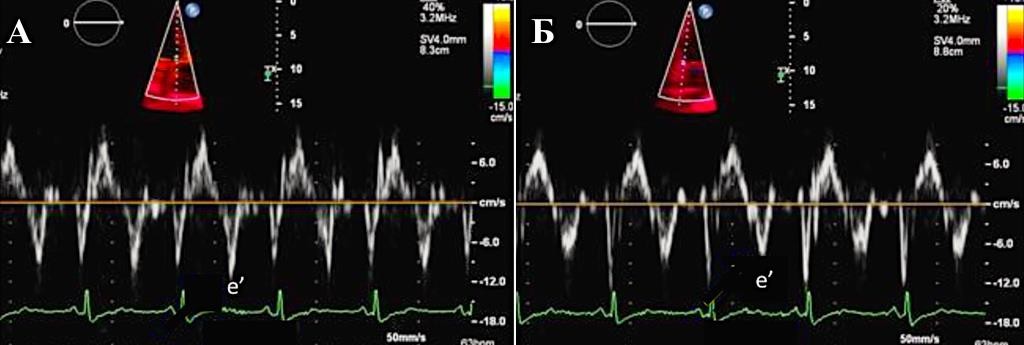

В диагностике констриктивного перикардита также может быть полезна тканевая допплерография, демонстрирующая так называемый феномен “annulus reversus”, заключающийся в том, что нормальная или повышенная ранняя диастолическая скорость движения медиальной части митрального кольца (медиальная е') оказывается выше, чем ранняя диастолическая скорость движения латеральной части фиброзного кольца (латеральная е’) (Приложение А3, рис. 3) [117].

Сочетание разнонаправленного смещения МЖП в зависимости от фаз дыхания с увеличением ранней диастолической скорости движения медиальной части митрального кольца (медиальная е') ≥9 см/сек имеет самую высокую диагностическую чувствительность (87%) и специфичность (91%) [118].

Допплер-ЭхоКГ позволяет определить парадокс кольца. Он заключается в том, что при относительном сохранении способности миокарда растягиваться в продольном направлении деформация продольной оси левого желудочка и продольная ранняя диастолическая скорость либо нормальные, либо, по мере прогрессирования констриктивного перикардита, увеличиваются. В то время как при рестриктивной кардиомиопатии или при заболеваниях миокарда происходит снижение этих показателей. При этом усредненная максимальная тканевая скорость раннего диастолического смещения септальной части митрального кольца выше латеральной (Приложение А3, рис. 6) [117, 123, 124–128]. Несмотря на высокую чувствительность и специфичность (95% и 96% соответственно), ограничение данного признака при диагностике будет проявляться в случае неоднородности поражения перикарда или при кальцификации кольца митрального клапана.